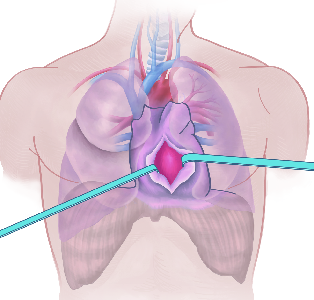

Detailreiche Fotografien aus der medizinischen Praxis ergänzen die Texte; moderne, genaue,

wissenschaftliche Zeichnungen geben Einblick in die Anatomie und die Funktion der Lunge und

anderer Organe.